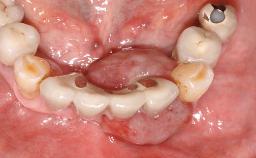

Oral implants are highly successful and offer long-term benefits, especially in the rehabilitation of edentulous patients or patients with oral defects following ablative tumor surgery (Albrektsson and coworkers 1986), and also after radiation therapy (Schiegnitz and coworkers 2014). With the number of implants placed globally going into the millions, implant dentists have observed some rare adverse events. Although carcinogenesis around implants is an exceedingly rare phenomenon, we recently reported about 15 patients treated for carcinomas adjacent to implants at our clinical department over a period of fifteen years (Moergel and coworkers 2014). The following case represents a patient of this cohort; it discusses possible risk factors and makes suggestions for a recall schedule. A 70-year-old woman was referred to our outpatient department for evaluation of a rapidly growing macroscopic alteration of the mucosa in the left mandible.

# of Implants 4